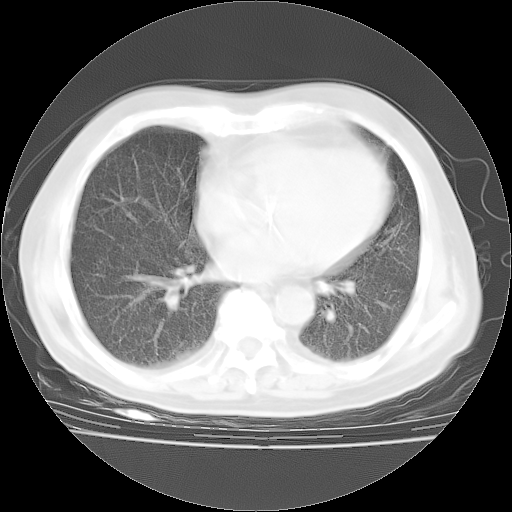

4月28日肺部CT